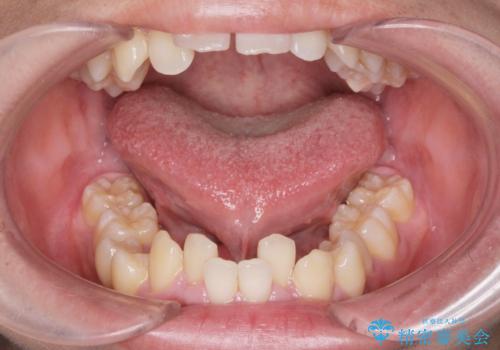

[ 舌小帯の形成術 ] ラ行の発音を改善したい

![[ 舌小帯の形成術 ] ラ行の発音を改善したいの症例 治療前](https://seimitsushinbi.jp/wp/wp-content/uploads/2024/08/acee470463c1189e4b61545af4154c68-500x350.jpg?v=1723775372)

![[ 舌小帯の形成術 ] ラ行の発音を改善したいの症例 治療後](https://seimitsushinbi.jp/wp/wp-content/uploads/2024/08/d2ed5db8e0b29e9cd54a7a382972d064-500x350.jpg?v=1723775393)